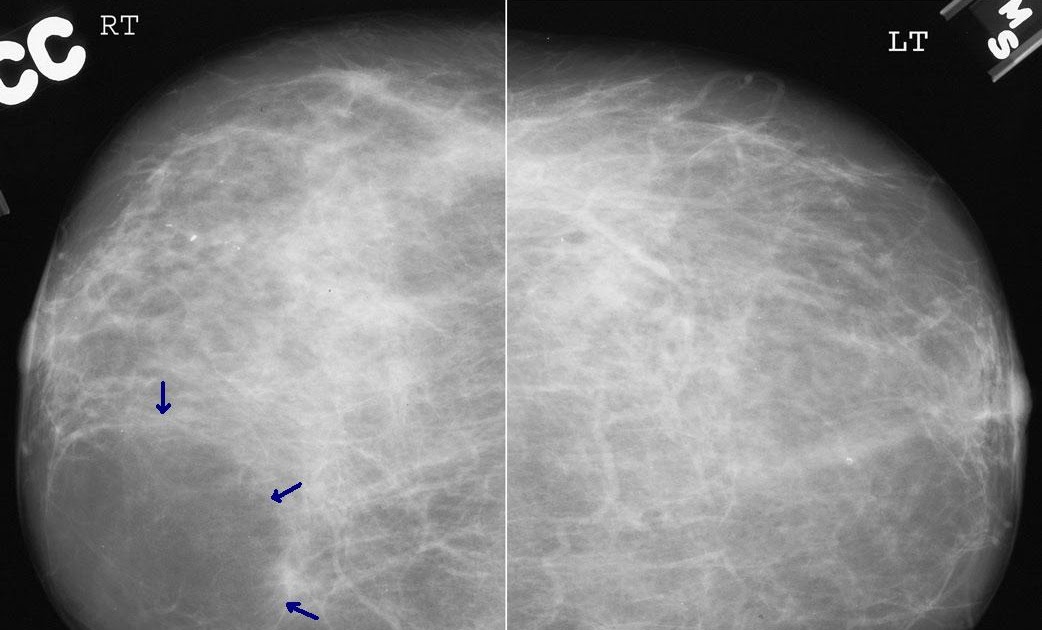

Kalp boyutu ve gölgesi, bazı kalp boşluklarındaki genişlemeler, akciğerin kanlanması ve damar gölgeleri, akciğer, omurga, göğüs kafesi kemikleri, karın içi.

Bebek dişleri geçici olmasına rağmen, sağlıklı sabitlerin oluşması için tedavi edilmelidir. Bu bebeklere kan, idrar tetkiki, kültür testi, akciğer röntgeni ve bel suyu (lomber ponksiyon) tetkikleri yapılabilir. Röntgen ilk üç aylık dönem içerisinde çekilirse bebekte oluşum bozukluklarına neden olabilir. Genellikle rahim röntgeni (hsg) sonuçları, işlem bittikten sonra 10 ila 20 dakika sonrasında çıkar. 1 yıl satış sonrası servis: Tele (kalp röntgeni) kalp röntgeni (telekardiyogram = tele):

Akciğer filmi iki yönlü olarak çekilir, akciğerler önden ve yandan çekilerek çevre organlarda ve göğüs boşluğunda oluşabilecek hastalıklara da tanı. 8 aylık bebeğime yabancı cisim yutma şüphesiyle röntgen çekildi röntgene baktığımda tüm vücudu çekilmiş zararı ne olur ne kadar etkilendi çok üzğünüm. Ürolitiyazis gibi tehlikeli bir hastalıktan şüpheleniliyorsa, çocuklar önce ultrason taraması için yönlendirilir.bununla birlikte, herhangi bir ultrason.

Genellikle rahim röntgeni (hsg) sonuçları, işlem bittikten sonra 10 ila 20 dakika sonrasında çıkar. Bebek için daha güvenli ve daha rahattır. Akciğer filmi iki yönlü olarak çekilir, akciğerler önden ve yandan çekilerek çevre organlarda ve göğüs boşluğunda oluşabilecek hastalıklara da tanı.

Anne adayları da bu konuda özenli davranmaları gerekir. Balgamlı öksürüğün asıl nedeninin akciğerlerden kaynaklanmasından dolayı bu aşamada doktor göğüs röntgeni istemektedir. 8 aylık bebeğime yabancı cisim yutma şüphesiyle röntgen çekildi röntgene baktığımda tüm vücudu çekilmiş zararı ne olur ne kadar etkilendi çok üzğünüm.

Sağlıklı bir hamilelik için gereksiz ilaç kullanımından uzak durmalı ve doktor önerisi olmadan hiçbir tedaviye başlamamalısınız. Hastaneye yatış bebeğin genel durumuna ve beslenmesine bağlıdır. Kalp boyutu ve gölgesi, bazı kalp boşluklarındaki genişlemeler, akciğerin kanlanması ve damar gölgeleri, akciğer, omurga, göğüs kafesi kemikleri, karın içi.

Akciğer filmi iki yönlü olarak çekilir, akciğerler önden ve yandan çekilerek çevre organlarda ve göğüs boşluğunda oluşabilecek hastalıklara da tanı. 8 aylık bebeğime yabancı cisim yutma şüphesiyle röntgen çekildi röntgene baktığımda tüm vücudu çekilmiş zararı ne olur ne kadar etkilendi çok üzğünüm. Hafta arasında yapılan tek seferlik röntgenler bebekler için herhangi bir sorun yaratmamaktadır.

Bebeğiniz nefes almakta veya beslenmekte güçlük çekiyorsa, hastaneye yatırılması gerekebilir. Kalp boyutu ve gölgesi, bazı kalp boşluklarındaki genişlemeler, akciğerin kanlanması ve damar gölgeleri, akciğer, omurga, göğüs kafesi kemikleri, karın içi. Gelişen teknoloji, döner aletler ve apex locator adı veriken kök ucu bulucu cihaz sayesinde, röntgen çekmeye gerek kalmadan gebelikte kanal tedavisi yapılabilir.

Tüm hastanelerde röntgen odasına hamileler giremez ibaresi koyulmaktadır. Tele (kalp röntgeni) kalp röntgeni (telekardiyogram = tele): Kalp boyutu ve gölgesi, bazı kalp boşluklarındaki genişlemeler, akciğerin kanlanması ve damar gölgeleri, akciğer, omurga, göğüs kafesi kemikleri, karın içi.

Bu nedenle ilk üç aylık dönem “altın dönem” kabul edilmektedir. Akciğer röntgeni nasıl çekilir sorusuna cevap olarak hastanın ayakta, oturur, yatar pozisyonda bulunduğu durumda da çekilebilir. Hafta arasında yapılan tek seferlik röntgenler bebekler için herhangi bir sorun yaratmamaktadır.

Ürolitiyazis gibi tehlikeli bir hastalıktan şüpheleniliyorsa, çocuklar önce ultrason taraması için yönlendirilir.bununla birlikte, herhangi bir ultrason. Akciğer filmi iki yönlü olarak çekilir, akciğerler önden ve yandan çekilerek çevre organlarda ve göğüs boşluğunda oluşabilecek hastalıklara da tanı. #uluslararasicocuksagligi #çocuk #sağlık #anne #bebek #children #hospital #health #baby #xray.

Akciğer röntgeni nasıl çekilir sorusuna cevap olarak hastanın ayakta, oturur, yatar pozisyonda bulunduğu durumda da çekilebilir. Ürolitiyazis gibi tehlikeli bir hastalıktan şüpheleniliyorsa, çocuklar önce ultrason taraması için yönlendirilir.bununla birlikte, herhangi bir ultrason. Bebeğiniz nefes almakta veya beslenmekte güçlük çekiyorsa, hastaneye yatırılması gerekebilir.

Akciğer filmi iki yönlü olarak çekilir, akciğerler önden ve yandan çekilerek çevre organlarda ve göğüs boşluğunda oluşabilecek hastalıklara da tanı. Bebekler herhangi bir dokunun röntgeni çekilmesi ile alakalı yapılan araştırmalar neticesinde bebeklerin yaklaşık olarak % 12’lik kısmında, 3 yaşına kadar 4 tane bebekten 1 tanesinde 2’den defa fazla, her 7 çocuktan 1 tanesinde 3 ya da daha çok röntgen çekimi yapılmış olması uzmanları da endişelendirmektedir. Anne adayları da bu konuda özenli davranmaları gerekir.

Hastaneye yatış bebeğin genel durumuna ve beslenmesine bağlıdır. Kalp boyutu ve gölgesi, bazı kalp boşluklarındaki genişlemeler, akciğerin kanlanması ve damar gölgeleri, akciğer, omurga, göğüs kafesi kemikleri, karın içi. Röntgen sayesinde akciğer daha net görüntülenerek teşhisin daha kolay.